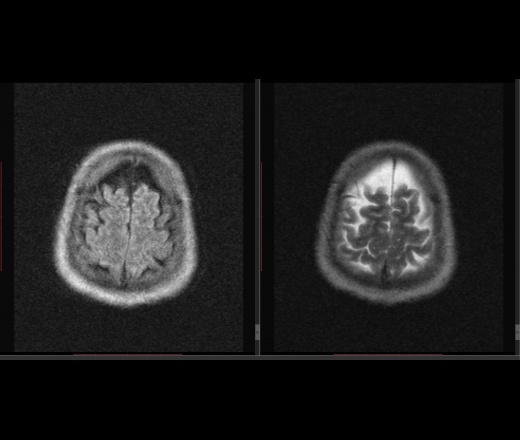

Мужчина 1964 г.р. Жалобы на нарушение памяти, снижение зрения и кратковременную потерю сознания, температура нормальная.

Я думаю что это может быть какой нибудь васкулит, либо Posterior Reversible Encephalopathy Syndrome, о чем можно думать в данном случае?

eto pres

Я представлял синдром с более выраженным изменением сигнала от белого вещества и меньшим - коры.